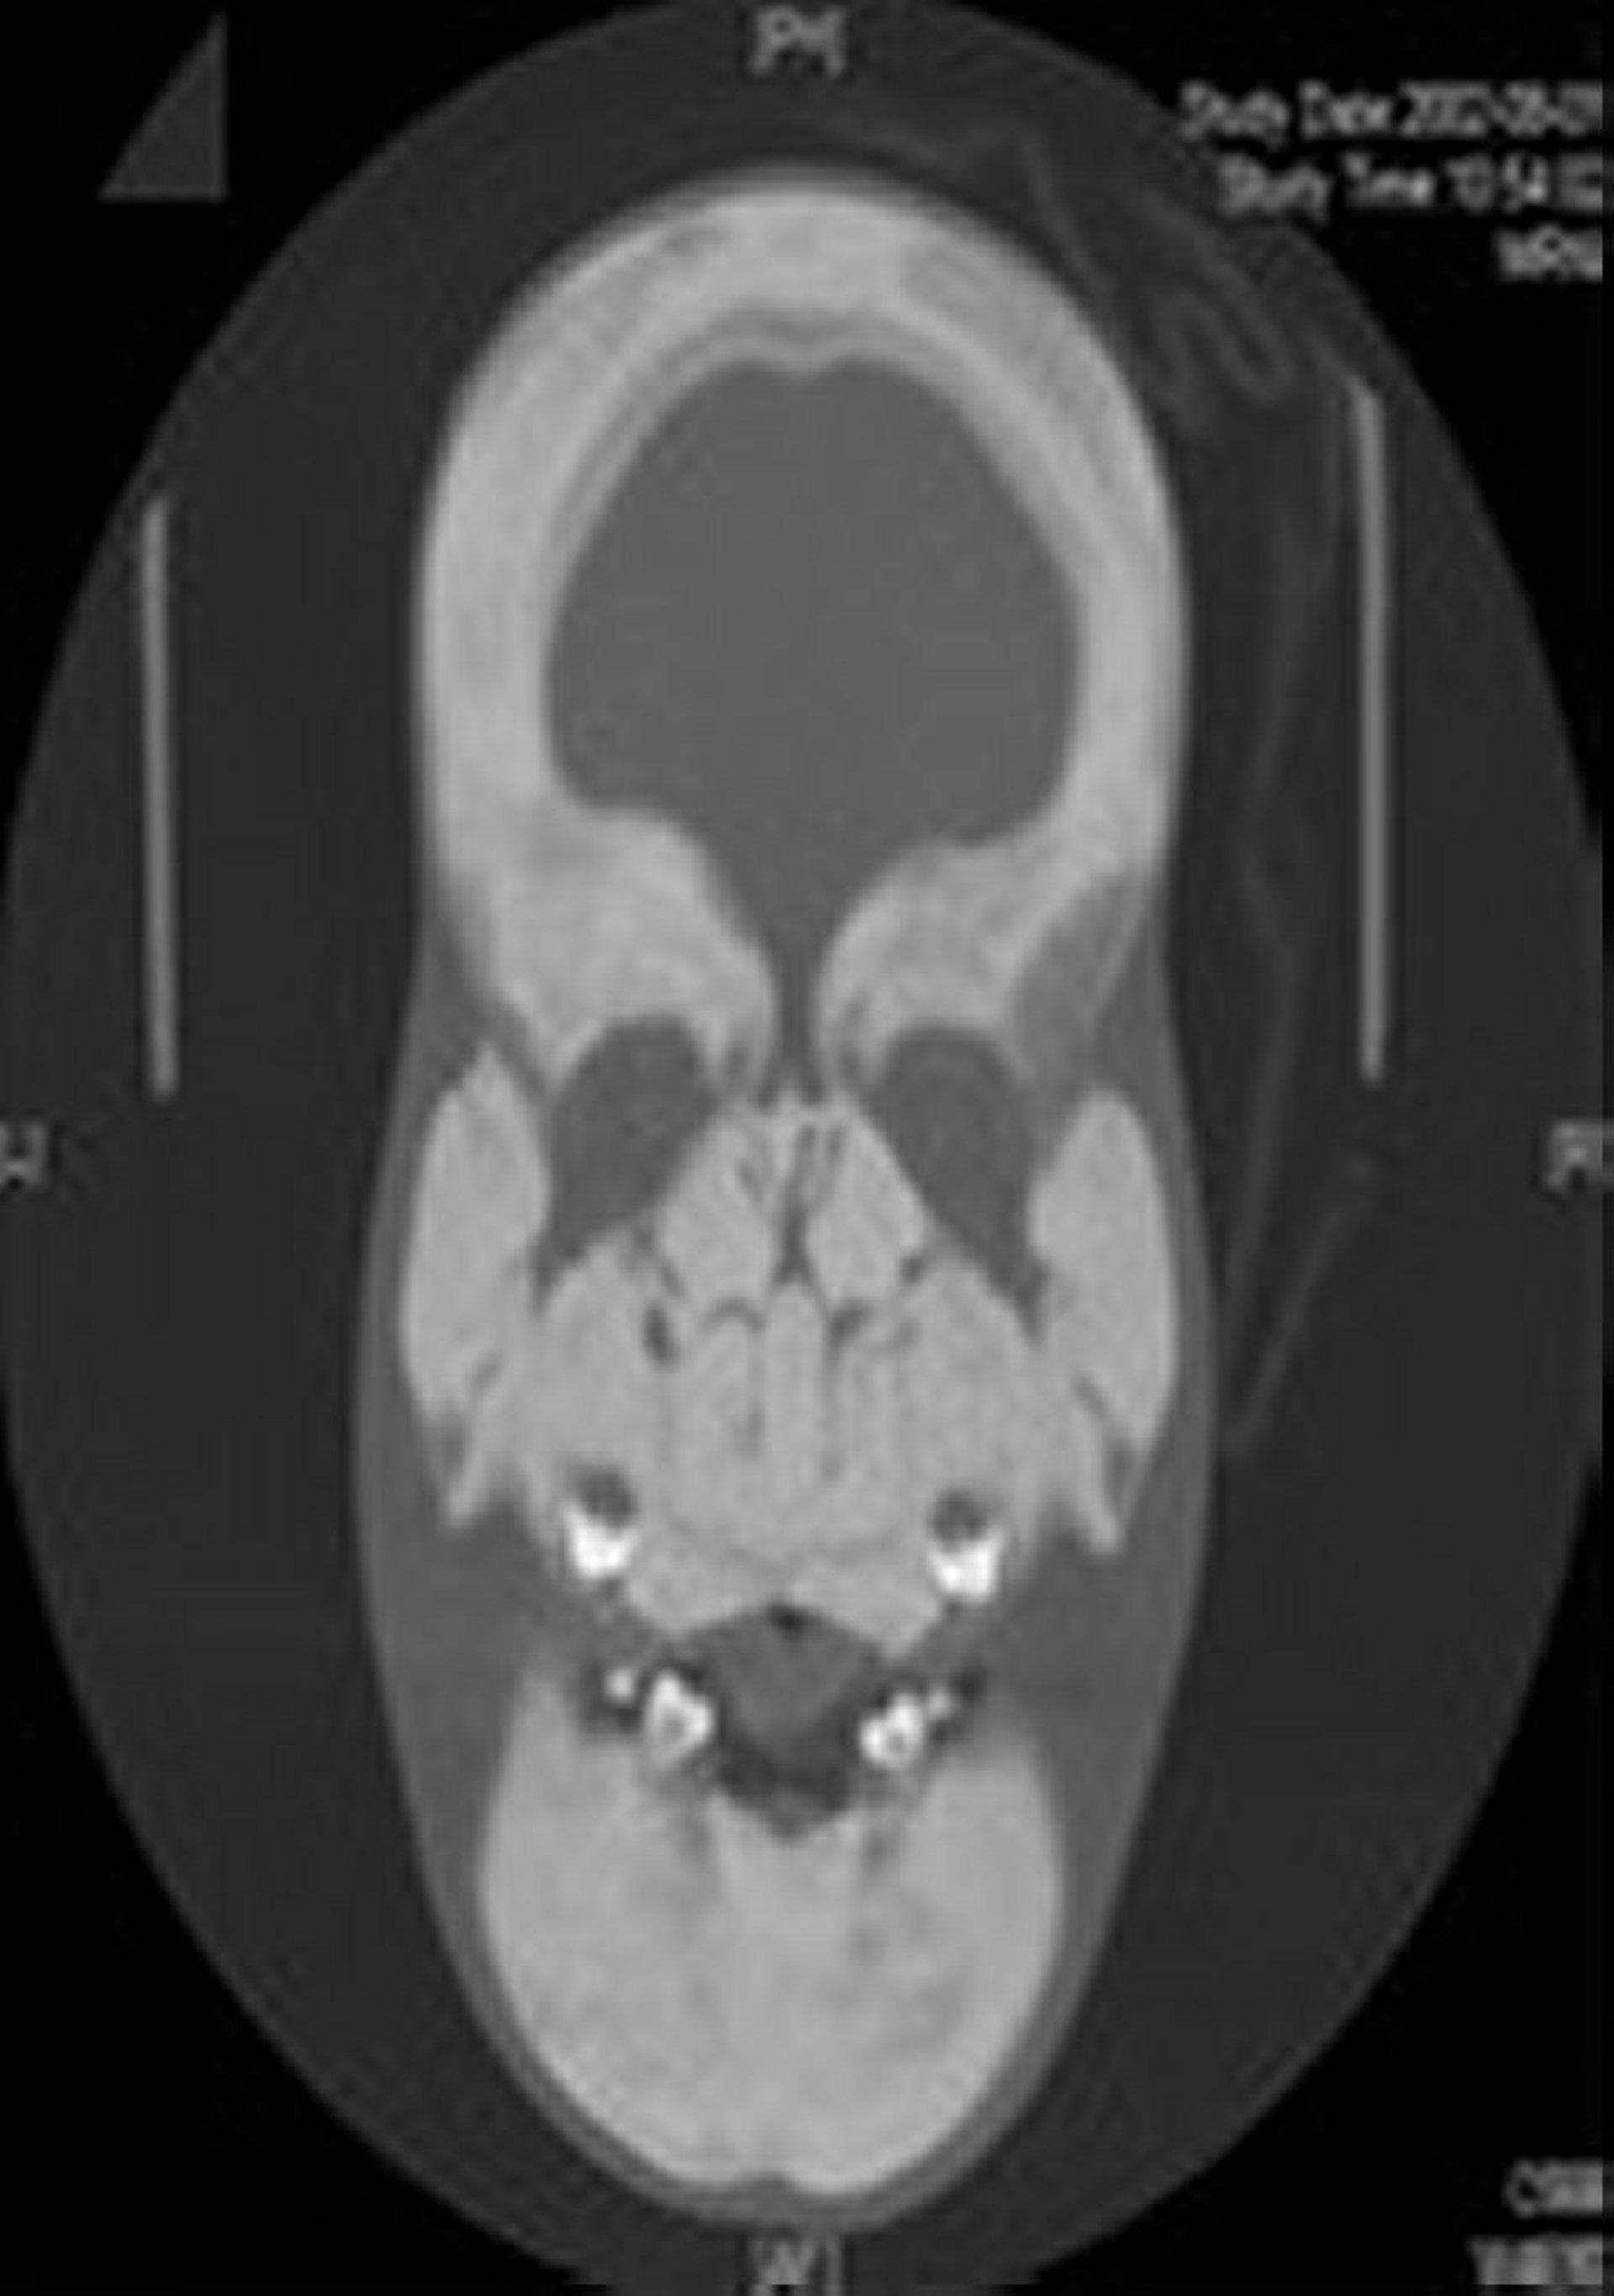

© Springer Science+Business Media

Le diagnostic de la sclérostéose est suspecté sur des anomalies squelettiques caractéristiques, en particulier lorsque le patient a également une syndactylie. Typiquement, des radiographies simples sont effectuées. L'élargissement et la sclérose marqués de la voûte crânienne et de la mandibule sont les principales caractéristiques de la radiographie du crâne. Les corps vertébraux sont indemnes, bien que leurs pédicules soient condensés. Les os du bassin sont denses, mais gardent des contours normaux. Les os longs sont denses, avec des corticales épaissies et mal modelées. Un test diagnostique génétique est disponible.